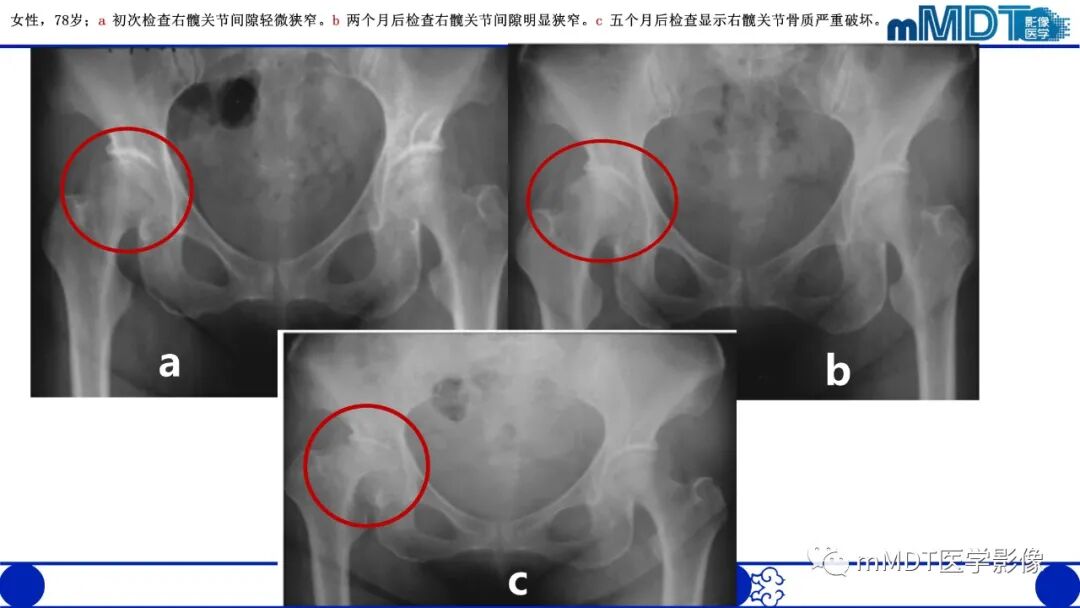

1.平片、CT:活动期表现骨质疏松,股骨头和转子间弥漫性骨密度减低,股骨头软骨下骨皮质吸收,髋臼受累程度轻,无骨侵蚀或破坏,关节间隙保持正常。